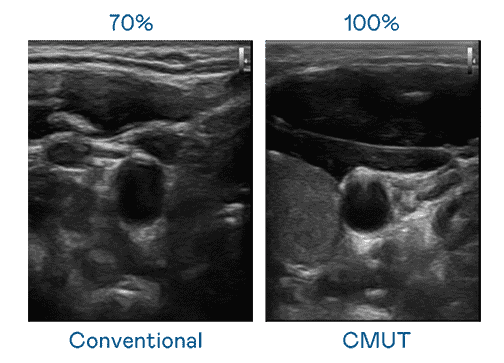

CMUT 技术是一种用电容式微机电元件来产生超音波讯号的技术。。。与传统 PZT 压电式技术相比,,CMUT 频宽增加 30%,,,更宽频的超音波讯号让影像解析度大幅提升,,,,是实现高影像品质医疗超音波扫描、、、、促进精准医疗发展的关键技术。。

超音波影像的解析度高低,,,首先取决于探头能发出的讯号频宽。。银河集团 CMUT 可提供高清晰的超音波讯号,,,提供高频宽、、、高灵敏度、、、影像纹理细节更高的超音波影像,,协助医护人员缩短影像判读时间及利用精准的医疗影像进行诊断。。